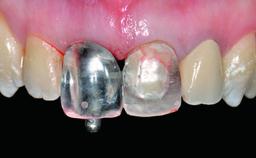

Loading Protocol Conventional or early

Retention Screw-retained Screw-retained

Provisional Implant-Supported Prosthesis Prosthodontic margin > 3 mm apical to mucosal margin Prosthodontic margin > 3 mm apical to mucosal margin

Interim Prosthesis during Healing Fixed Fixed